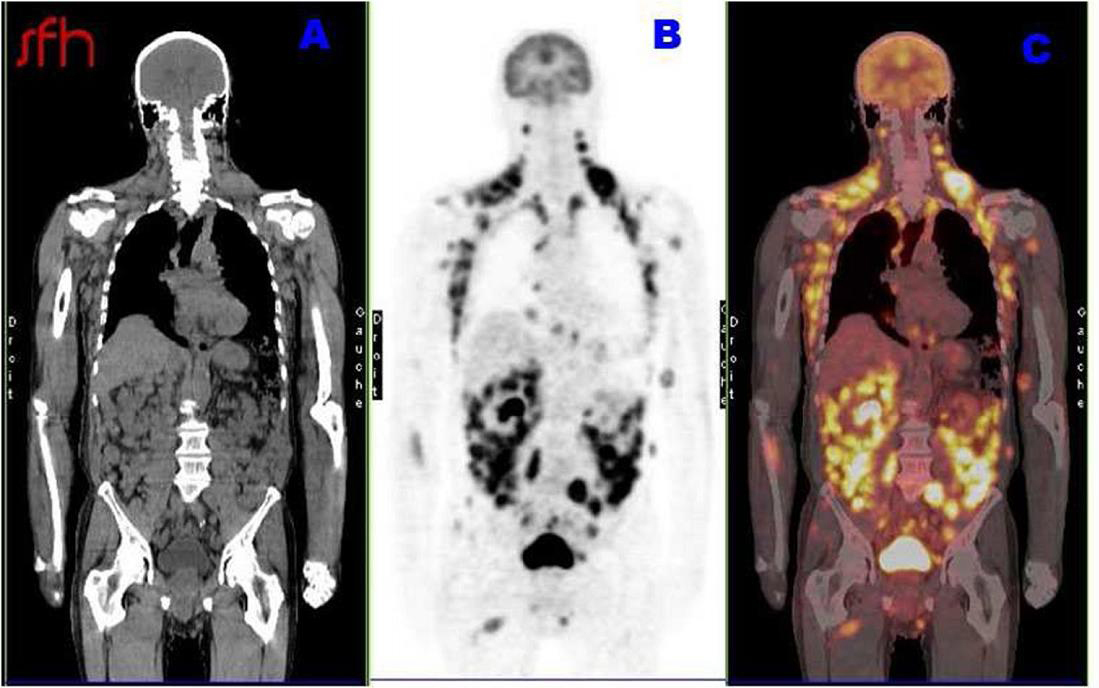

Maxime, 21 ans, étudiant en droit, se présente à votre consultation pour une asthénie trainante et s’intensifiant depuis un mois, responsable d’un absentéisme professionnel. Il a maigri de 5 kg ces trois derniers mois (poids actuel 72 kg pour un poids de forme à 77 kg) et souhaiterait que vous lui prescriviez des vitamines. Il se plaint de démangeaisons sur tout le corps, d’une toux sèche et de lombalgie mal calmée par 4 g de paracétamol. À l’anamnèse, ce dernier vous rapporte une fébricule vespérale à 38,5 °C au coucher disparaissant le matin au réveil. Par ailleurs, il rapporte des sueurs nocturnes particulièrement gênantes. Pas de voyage récent. À l’examen clinique, vous retrouvez des lésions de grattage dans le dos, une adénopathie sus claviculaire droite de 2,5 cm, une adénopathie inguinale droite de 3 cm et une splénomégalie à trois travers de doigt. Son bilan biologique est le suivant : natrémie : 140 mmol/L, kaliémie : 3,9 mmol/L, créatinémie : 73 µmol/L, Hb : 10,3 g/dL, VGM : 85 µm3, globules blancs : 8 G/L avec des polynucléaires neutrophiles à 2,5 G/L, des polynucléaires éosinophiles à 1,7 G/L et des lymphocytes à 2 G/L, plaquettes : 156 G/L, pas de cellules anormales circulantes. La VS est à 82 mm à 1 heure et la CRP 153 mg/L. Au regard de l’anamnèse et de l’examen clinique, vous décidez d’hospitaliser le patient pour élargir les explorations.